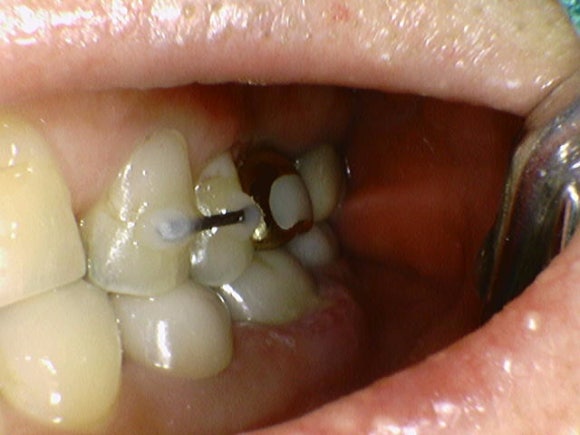

20240809

60대 남자분께서 오셨습니다.

왼쪽 아래 어금니를 발치해야 한다고 다른 치과에서 들으셨다고 합니다.

엑스레이를 보니

신경치료를 하고 크라운을 씌운 치아였는데,

크라운 하방의 충치가 너무 심해서

남아있는 치아가 거의 없는 상태였습니다.

"치아머리가 많이 상해있어서 재신경치료를 한다 한들, 나중에 머리를 다시 만들 수가 없겠습니다."

"발치하시는 것이 좋겠습니다"

안타까운 마음이었습니다.

조금이라도 남아있으면 레진파이버 기둥을 세워서 머리 부분을 보강할 수 있었을텐데 말입니다.